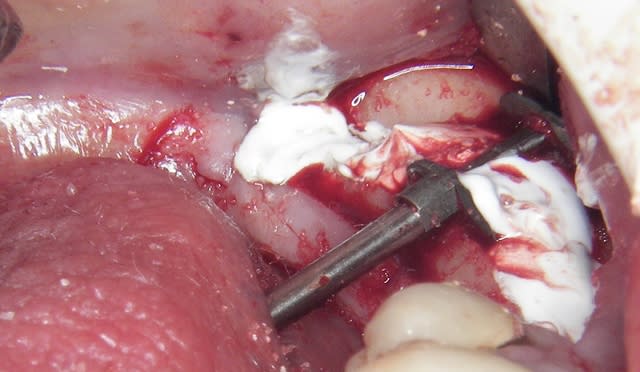

> dans le cas présenté, j'ai d'abord mis du perioglass (billes) que j'ai compacté

> "légèrement" à la compresse+Ostéotome pour "bloquer" la partie osseuse

> surélevée, puis j'ai mis le VitalOs que j'ai lui aussi "aplani" à la compresse +

> Ostéotome.

> Il maintient les billes, et les deux corticales et sert de membrane

J’ai donc fait une expansion verticale et latérale puisque je n’ai pas coupé la corticale linguale, du moins dans sa partie postérieure, et j’espère gagner sur les deux tableaux, mais il était risqué de mettre en plus les implants.

J’ai une tranchée finale qui fait 8 à 9 mm moins 1 mm du trait de coupe donc il faudrait une triangulation pour le calcul mais je verrais les coupes scan une fois solidifié c’est + simple)

quelques photos en "grand"

--